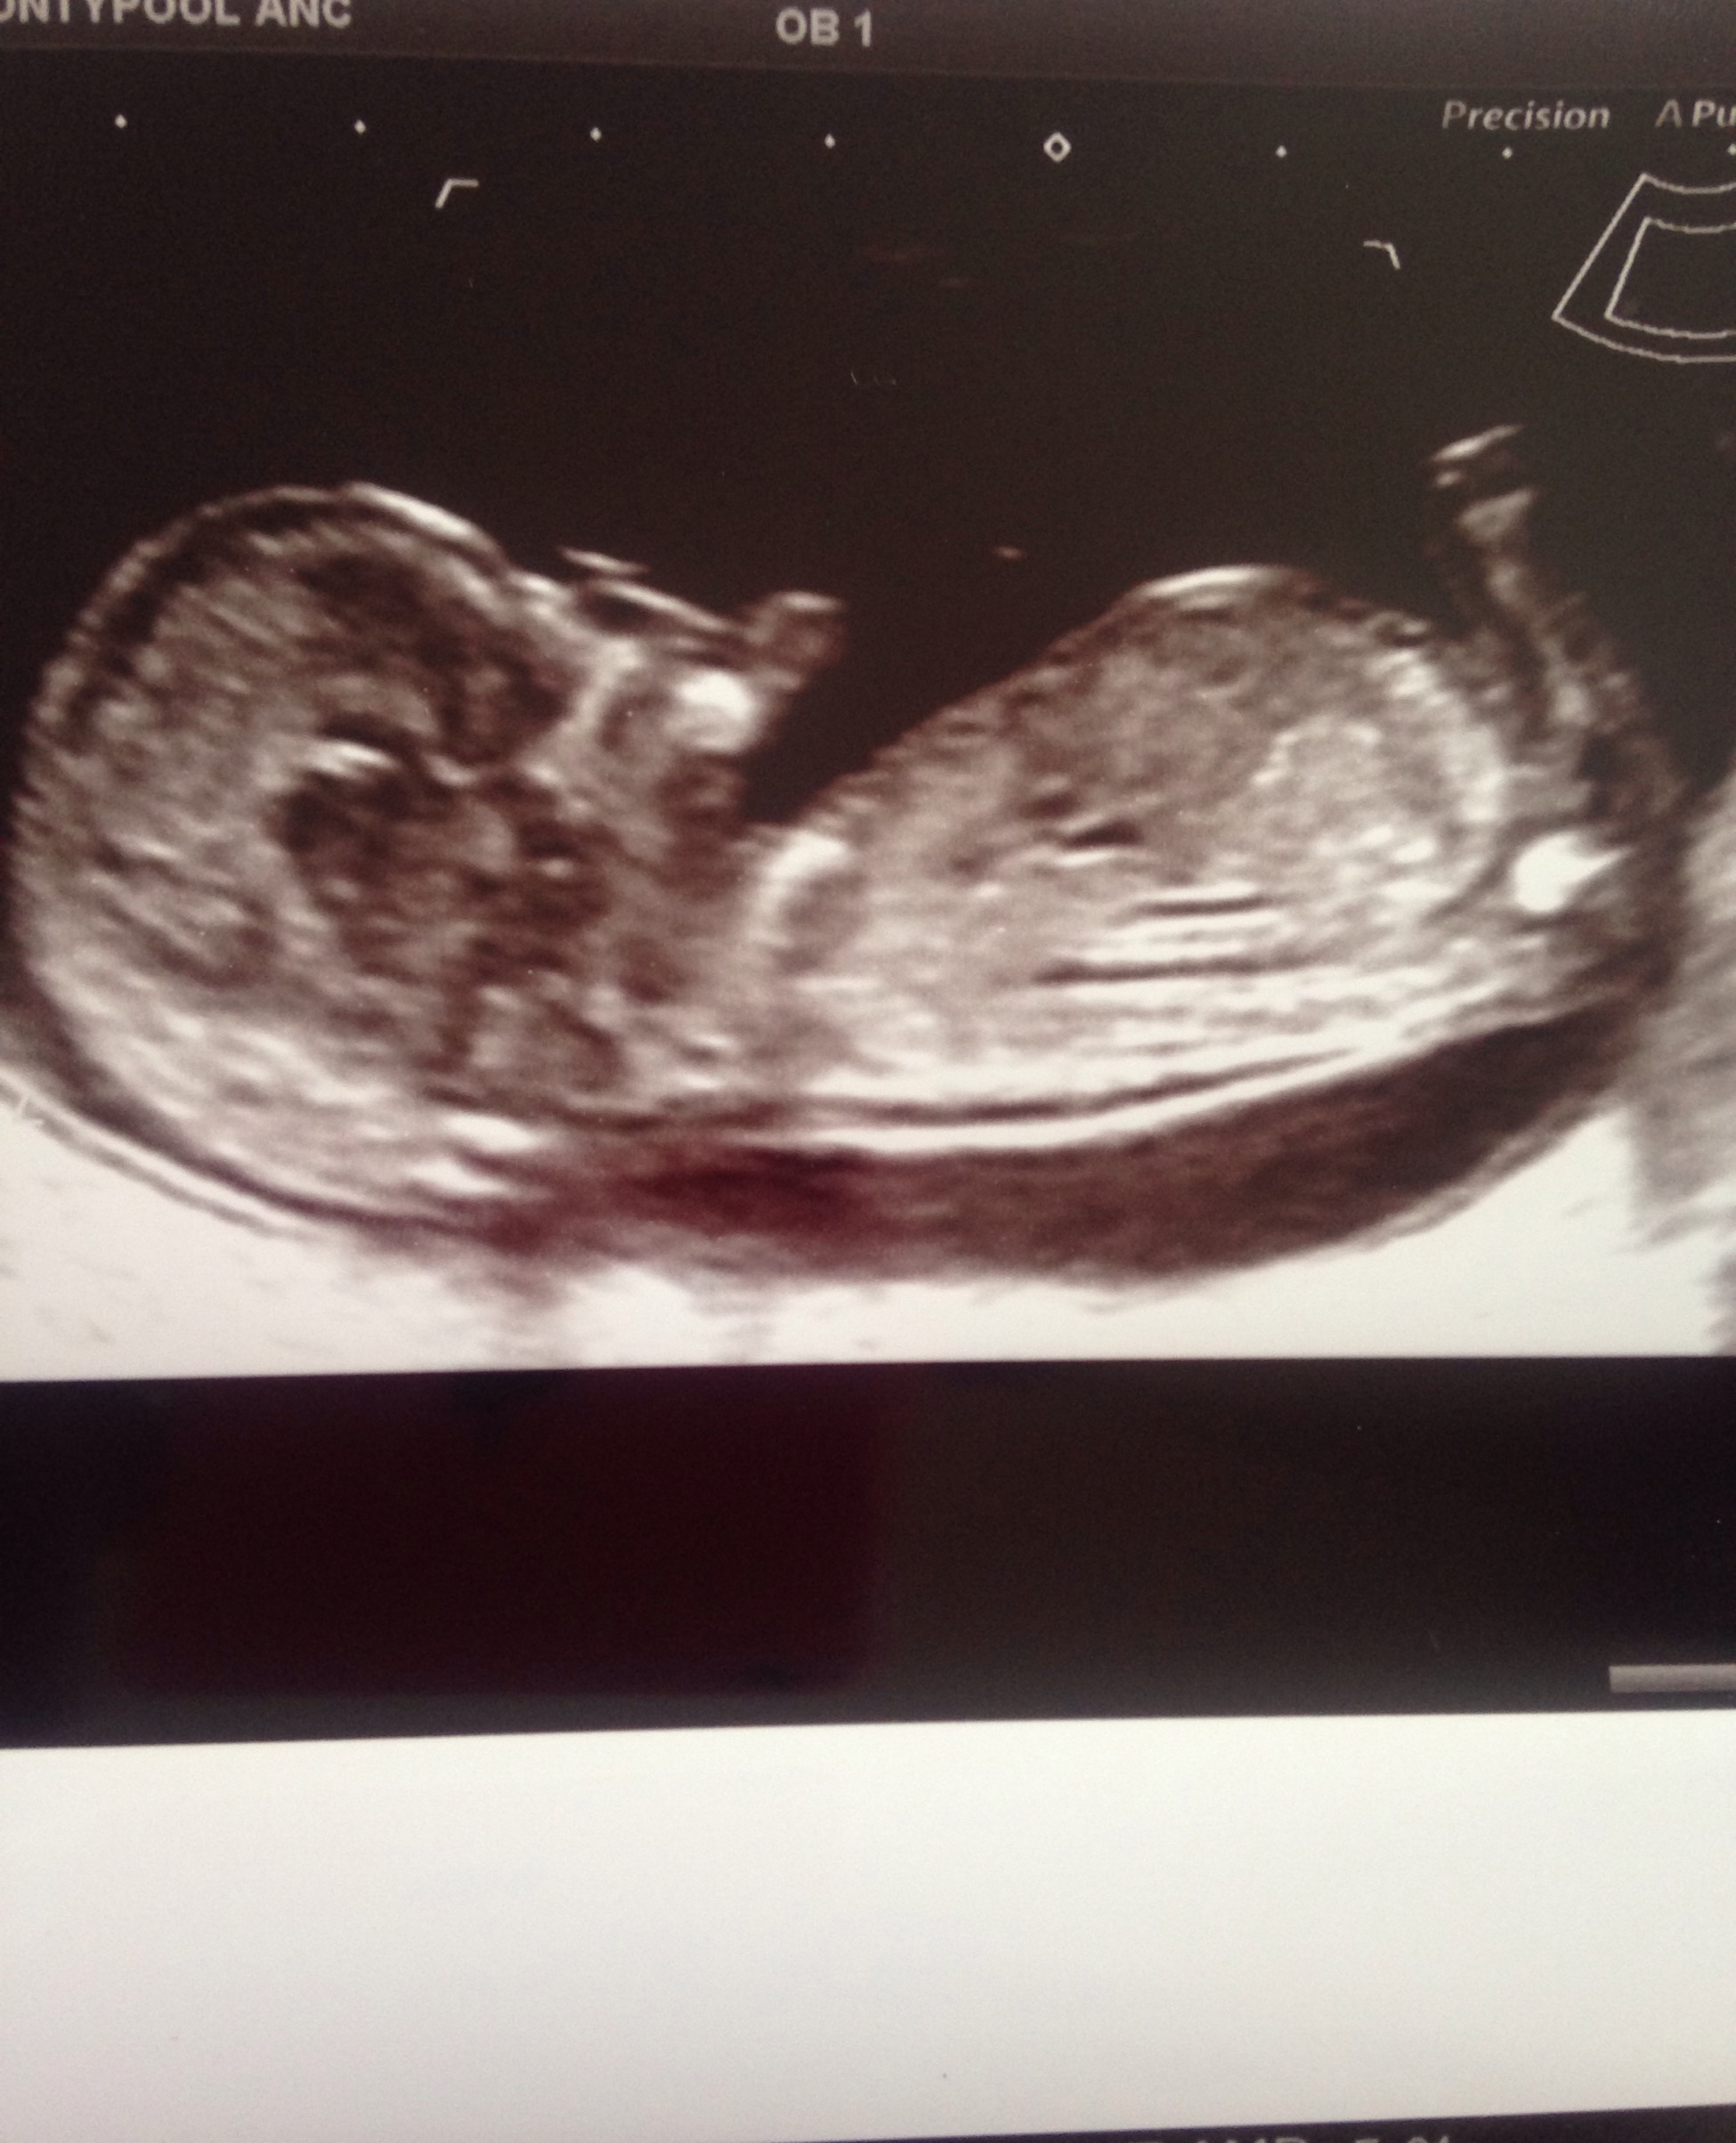

Ho ladies 😂 Just wondering if anyone could have a go at guessing the gender of my baby? Thanks ❤️

No nub. :(

I don't see a nub either. Do you have any other pictures?

no clues, more pics?

Agree with the other comments, can't really make out a nub from this shot sorry xx